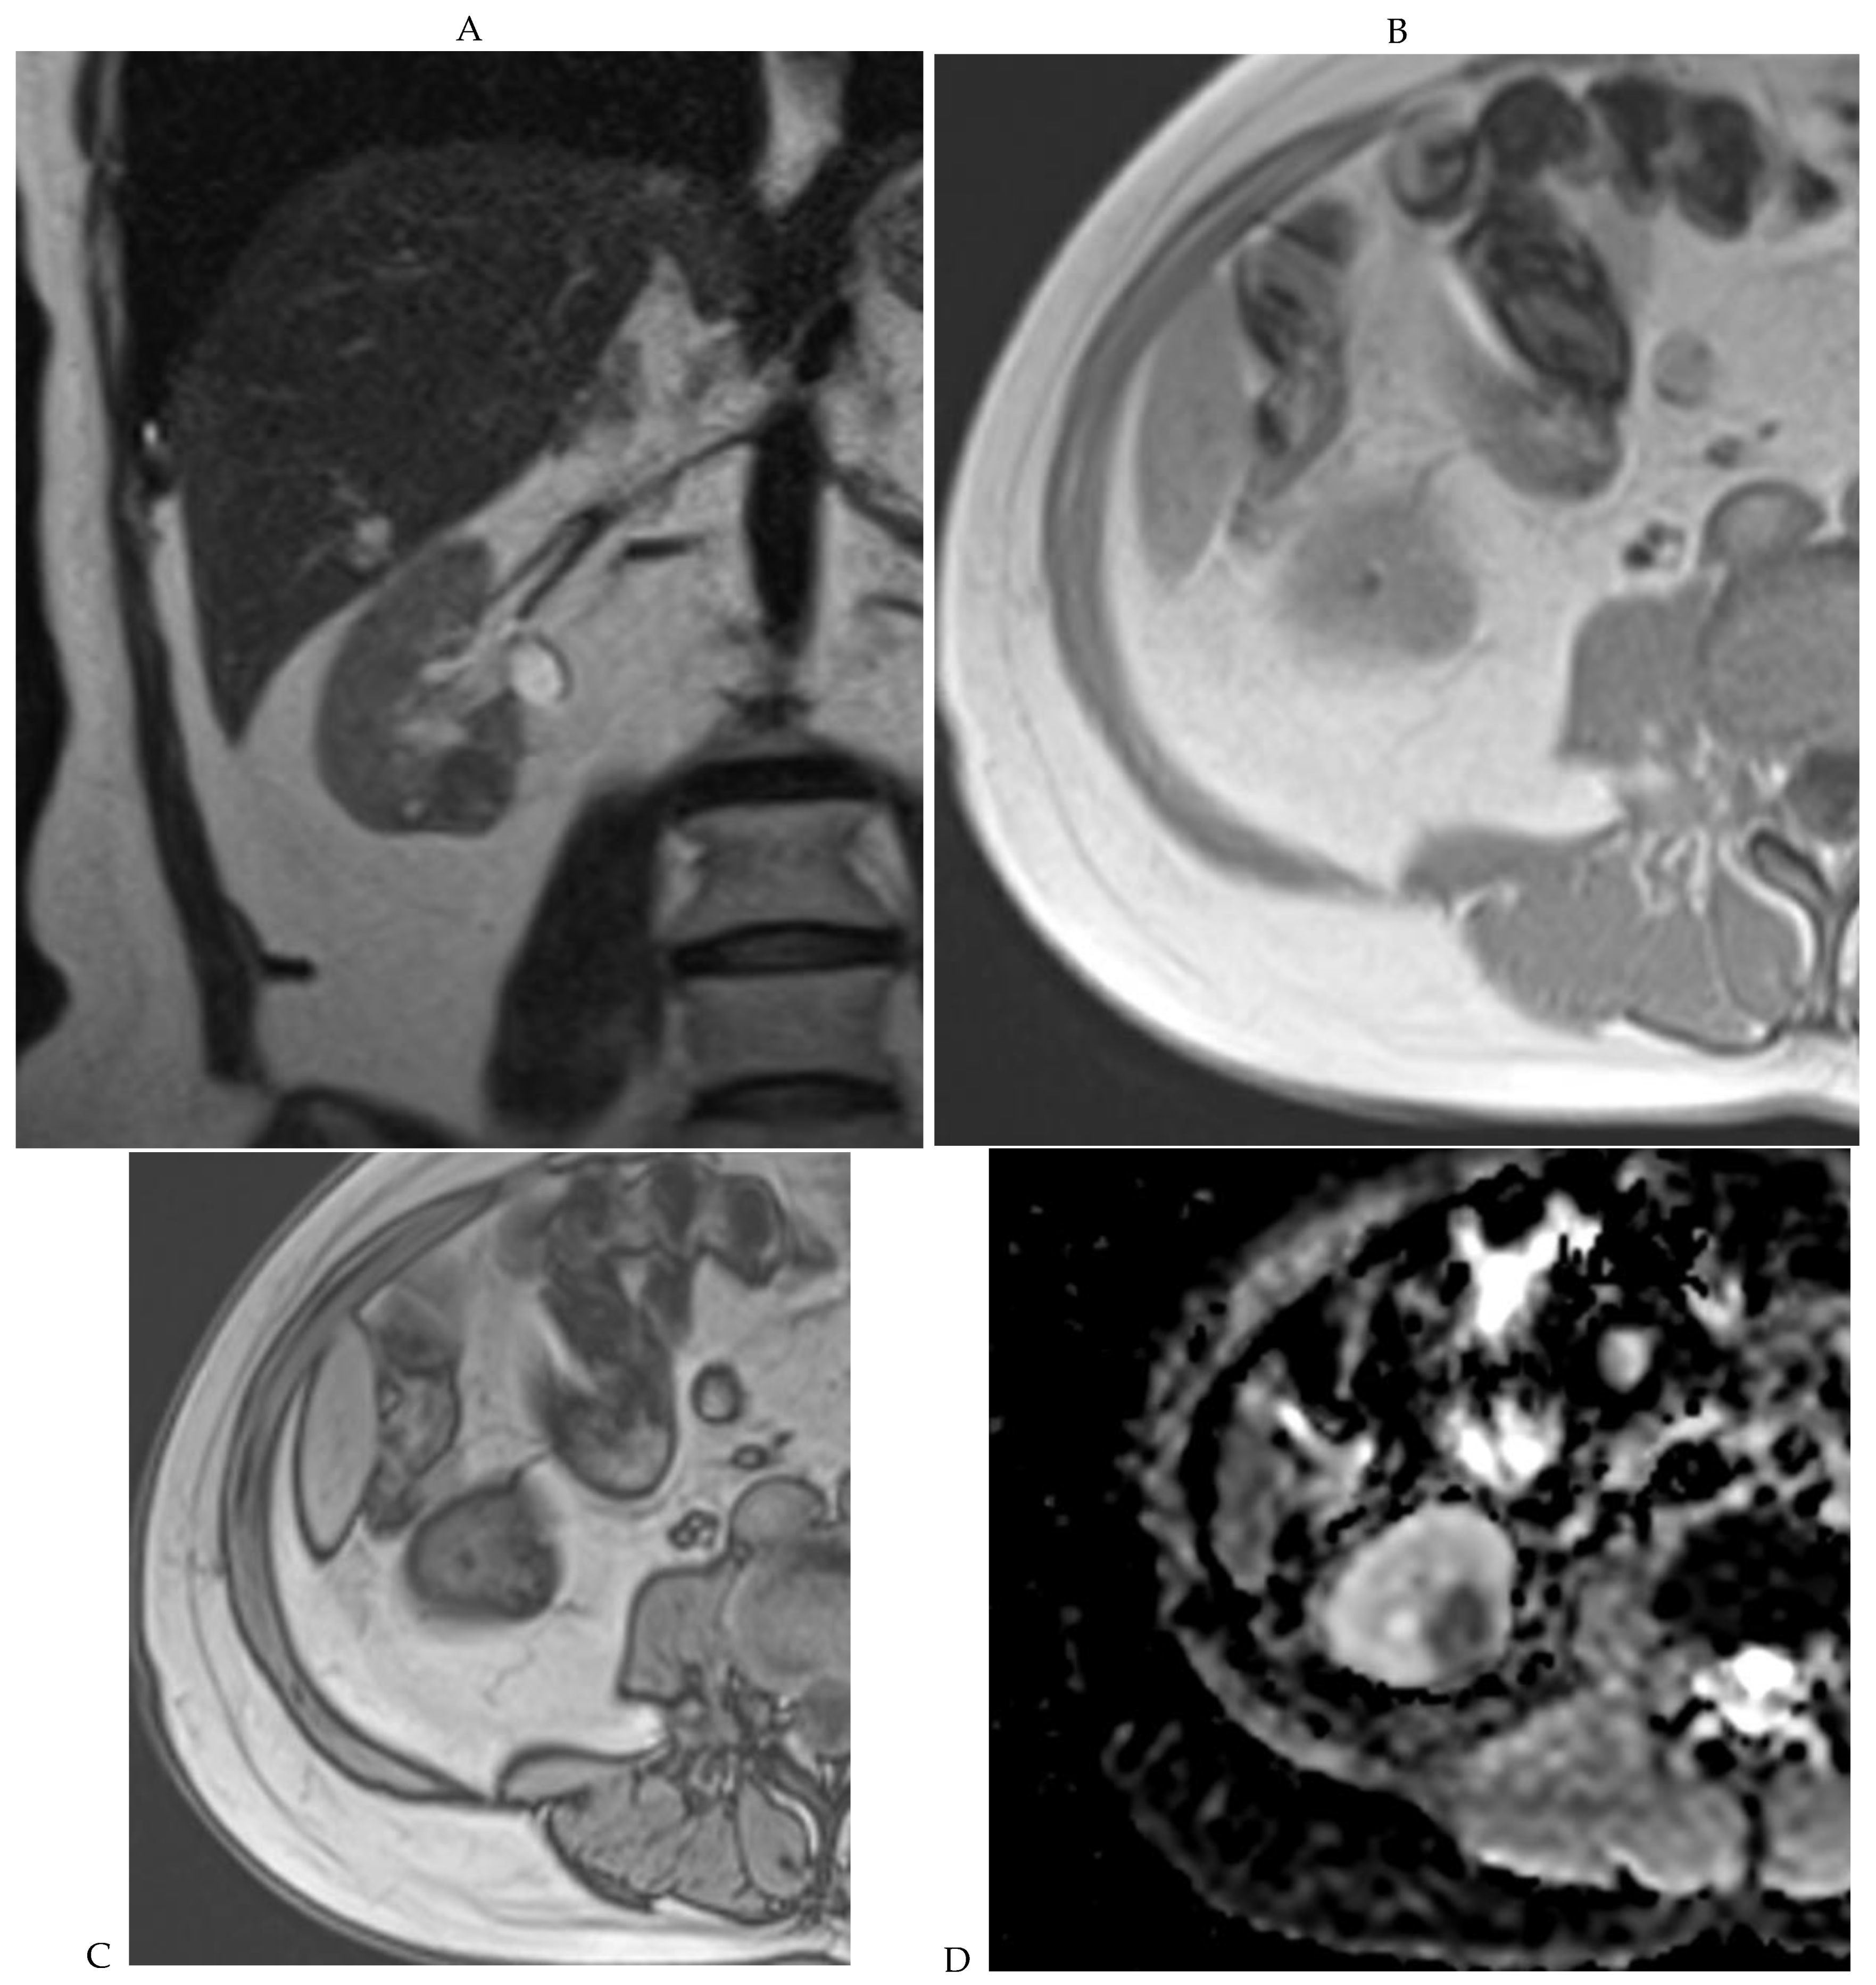

Figure 7.

Papillary renal cell carcinoma in the right kidney of a 75-year-old-woman. (A) Axial T2-weighted fast SE image shows a homogeneous 1.8 cm mass in the posterolateral region of the right kidney, with a lower SI compared to renal parenchyma. Transverse in-phase (B,C) opposed-phase MR images do not show a significant signal loss on the opposed-phase image. (D) The ADC map shows restriction of tumor diffusion into the renal mass. Transverse nonenhanced (E) and gadolinium-enhanced T1-weighted gradient-echo spoiled MR images in (F) corticomedullary, (G) nephrographic, (H) and delayed phase images show progressive enhancement without washout; the mass is hypovascular compared to the renal cortex.